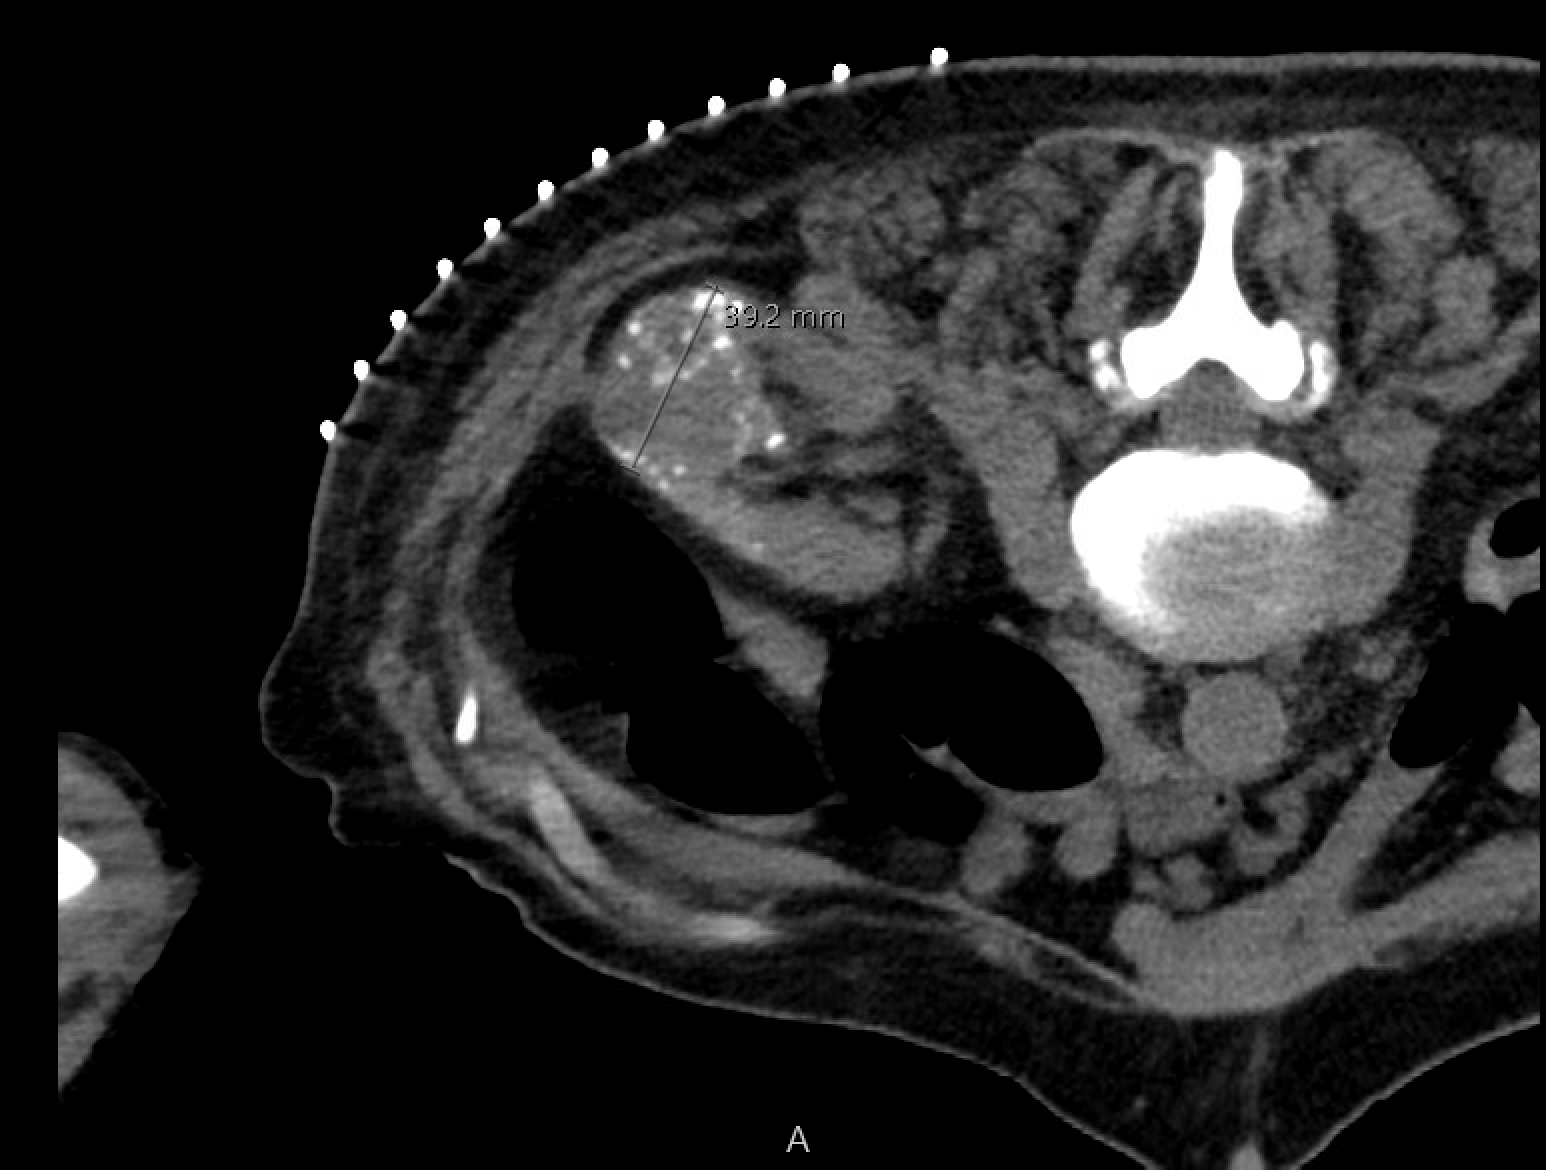

Cryoablation cycle: 10 min freeze → 8 min passive thaw → 10 min freeze (two-cycle standard). Intermittent CT confirms ice-ball growth and margin. Target 5–10 mm ice-ball margin beyond tumor edge (cytotoxic −20°C to −40°C isotherm is several mm inside the visible edge).

CT during cryoablation showing ice ball encompassing the renal mass — the hypodense ice ball should extend 5–10 mm beyond the tumor edge to achieve adequate lethal margin.